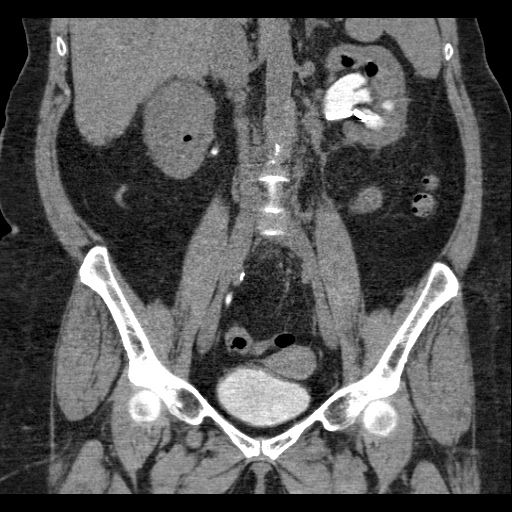

КТ ретроперитонеального фиброза: Изображения и диагностика